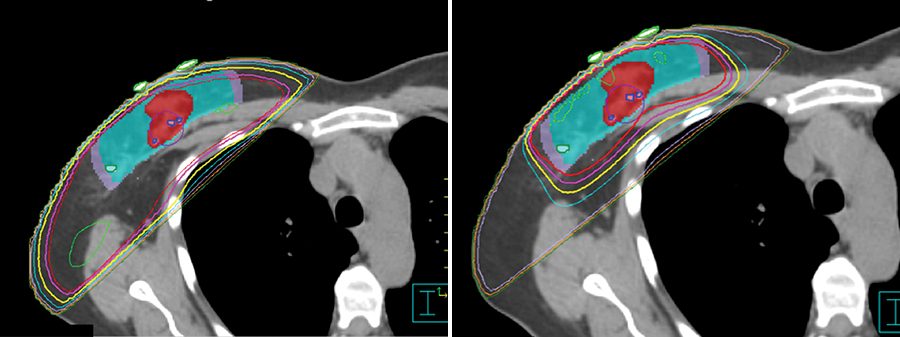

Irradiación hipofraccionada de mama parcial

Ensayo clínico prueba régimen de radioterapia de haz externo durante 10 días después de tumorectomía para pacientes con cáncer de mama de estadio inicial